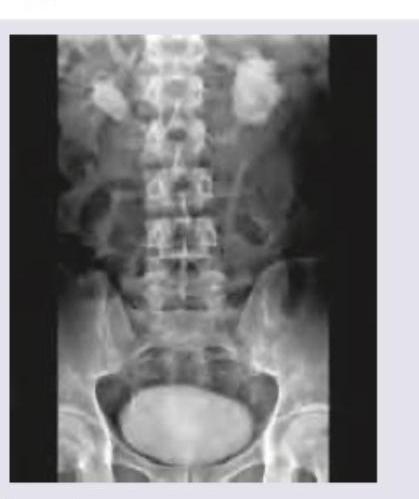

The following IVU shows:

Explanation: ***Horseshoe kidney*** - The image shows both kidneys are **fused at their lower poles** across the midline, forming a "horseshoe" shape, which is a classic radiographic finding for this condition. - The **calyces and renal pelves are seen medially oriented**, supporting the diagnosis of a horseshoe kidney. *Hydronephrosis* - **Hydronephrosis** would appear as a dilation of the renal pelvis and calyces due to obstruction, which is not the primary finding here. - While a horseshoe kidney can be associated with hydronephrosis due to an abnormal ureteral course, the image clearly depicts the **fused renal parenchyma** rather than just dilation. *Polycystic kidney* - **Polycystic kidneys** are characterized by numerous cysts of varying sizes replacing normal renal parenchyma, which would present as enlarged, multi-cystic kidneys on imaging. - The image does not show multiple cysts replacing the renal tissue but rather a **fused, single-mass structure** in the lower abdomen. *Duplication of collecting system* - **Duplication of the collecting system** involves two ureters draining a single kidney, or a bifid renal pelvis, which would appear as double ureters or collecting systems on an IVU. - This condition does not present with the characteristic **fusion of the renal poles** across the midline as seen in the image.